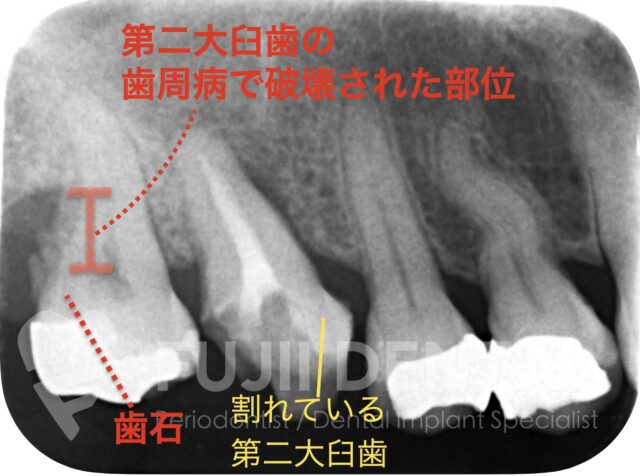

左上の後ろから2番目の奥歯(第一大臼歯)が割れ、歯の周りの組織が膿んで歯肉に穴が空いていました。この歯を残すことはできません。一方、レントゲンでは、一番奥の歯(第二大臼歯)に大きな歯石が付着し、歯周ポケットは8mm。骨の半分近くが失われている重度歯周病でした。

治療計画としては、2本抜歯してインプラント治療を行う選択肢も考えられましたが、後方の第二大臼歯は歯周病治療を行って残す方針としました。